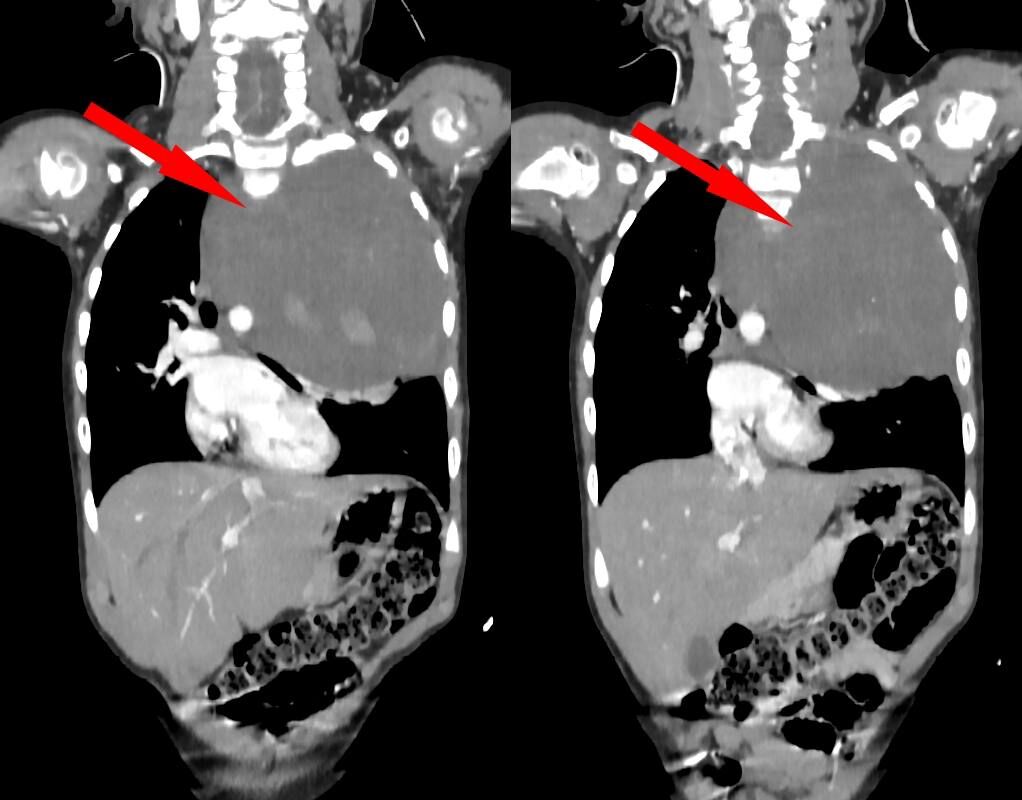

Родители показали дочь врачам, когда заметили у нее небольшую припухлость в области шеи. Специалисты по месту жительства выявили огромное новообразование размером со страусиное яйцо, которое сдавливало сердце и легкое. Сквозь ткань опухоли проходили крупные сосуды: «позвоночная артерия, питающая головной мозг, и подключичная артерия с ее ветвями, питающая левую руку». После телемедицинской консультации ребенка направили в Москву.

«Учитывая гигантский размер опухоли и ее расположение вблизи множества жизненно важных структур, мы использовали расширенный доступ по типу «раковины моллюска». Он предполагает рассечение не только межреберного промежутка, но и самой грудины, что позволяет «раскрыть» грудную клетку, как раковину», — рассказал заведующий отделением реконструктивной и восстановительной хирургии грудной полости РДКБ, к.м.н. Евгений Андреев об операции.